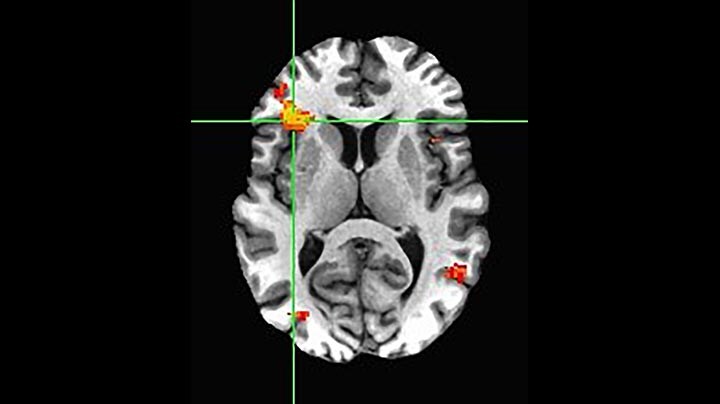

BOLD fMRI activation, depicted in color, of left anterior insula (MNI plane z = 8 mm) in a single subject by a contrast between viewing and matching faces with negative emotion (angry, sad, scared) versus happy faces. The voxelwise threshold is p < 0.001, and colored voxels survive false discovery rate correction to p < 0.05. The activated voxels in color are overlaid on the subject's own 3D-TFE image displayed in grayscale, after transforming the data to MNI space. The fMRI pulse sequence was a single shot FFE echo planar acquisition using MultiBand SENSE factor 6, dS SENSE factor 1, isotropic voxel size 2.4 mm, 60 transverse slices, TR 950 ms, TE 30 ms, flip angle 52 degrees, 517 dynamic scans, total scan duration 8:21 minutes. Image provided by James M. Bjork, PhD, Associate Professor of Psychiatry at VCU.

Imaging was performed using Ingenia 3T CX with a 32ch dS Head coil, TR 1.6 sec, TE 35 ms, voxel size 3.1 x 3.1 x 3.1 mm, 46 slices and Multiband SENSE factor 2. Image provided by Dr. Gispert

Default mode network as discovered by resting state fMRI in one participant of the ALFA cohort [7]. rs-fMRI allows us to find networks of brain regions with highly correlated activity and sustaining distinct brain functions. The default mode network (in warm color scale) is active when the brain is focused on introspective thinking and has been shown to be altered in Alzheimer’s. Interestingly, brain areas of this network are known to show abnormal levels of one of the pathological hallmarks of Alzheimer’s (b-amyloid deposition) in preclinical stages. We want to better understand the alterations of these brain networks in preclinical stages of Alzheimer's and explore their potential use as biomarkers.